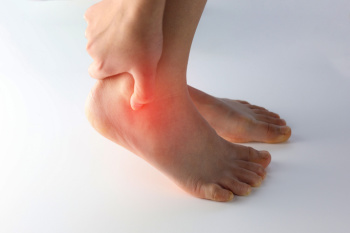

Ankle sprains in runners often develop from poor running form, uneven surfaces, wearing unsuitable footwear, or weak ankle muscles. Repetitive strain and lack of support can lead to inflammation, sprains, and chronic discomfort that limit performance. Preventing these injuries begins with gradual mileage increases, proper warm up and cool down routines, and strengthening exercises to enhance ankle stability. Wearing shoes designed for your foot type and replacing them regularly can also reduce stress on the joints. A podiatrist can assess your gait, identify underlying biomechanical issues, and recommend custom orthotics or rehabilitation strategies. For expert diagnosis and relief from ankle pain, it is suggested that you schedule an appointment with a podiatrist who can treat various foot conditions, and guide you on additional running injury prevention tips.

Ankle sprains are common but need immediate attention. If you need your feet checked, contact Neeta Hasmukh, DPM from Total Podiatry. Our doctor can provide the care you need to keep you pain-free and on your feet.

How Does an Ankle Sprain Occur?

Ankle sprains take place when the ligaments in your ankle are torn or stretched beyond their limits. There are multiple ways that the ankle can become injured, including twisting or rolling over onto your ankle, putting undue stress on it, or causing trauma to the ankle itself.

What Are the Symptoms?

- Mild to moderate bruising

- Limited mobility

- Swelling

- Discoloration of the skin (depending on severity)

Preventing a Sprain

- Wearing appropriate shoes for the occasion

- Stretching before exercises and sports

- Knowing your limits

Treatment of a Sprain

Treatment of a sprain depends on the severity. Many times, people are told to rest and remain off their feet completely, while others are given an air cast. If the sprain is very severe, surgery may be required.

If you have suffered an ankle sprain previously, you may want to consider additional support such as a brace and regular exercises to strengthen the ankle.